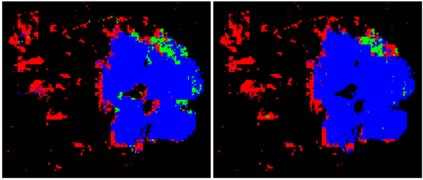

Prevention and early diagnosis of breast cancer (BC) is an essential prerequisite for the selection of proper treatment. The substantial pressure due to the increase of demand for faster and more precise diagnostic results drives for automatic solutions. In the past decade, deep learning techniques have demonstrated their power over several domains, and Computer-Aided (CAD) diagnostic became one of them. However, when it comes to the analysis of Whole Slide Images (WSI), most of the existing works compute predictions from levels independently. This is, however, in contrast to the histopathologist expert approach who requires to see a global architecture of tissue structures important in BC classification. We present a deep learning-based solution and framework for processing WSI based on a novel approach utilizing the advantages of image levels. We apply the weighing of information extracted from several levels into the final classification of the malignancy. Our results demonstrate the profitability of global information with an increase of accuracy from 72.2% to 84.8%.